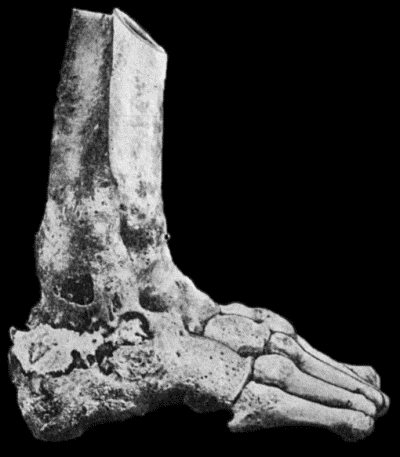

127.Advanced Tuberculous Disease in Region of Ankle 459